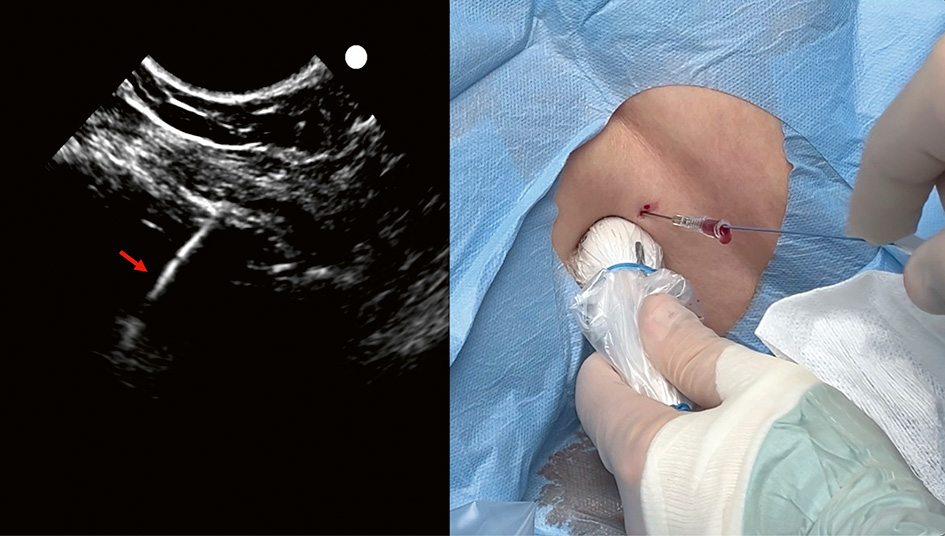

Pigtail-dräninläggning med realtids­ultraljud (A–F).

En video av proceduren kan hittas på https://www.youtube.com/watch?v=_yxGNKpZSiQ

C. Under direktvisualisering (»in plane«-teknik) används först en 21G 80 mm nål för att bedöva tänkt stickkanal. I samma stickkanal införs sedan under direktvisualisering den ihåliga 18G-nålen varigenom Seldinger-ledaren matas in. I bilden ses nålspetsen (pil) som ligger i den blodiga pleuravätskan. Stickriktningen är mot diafragma, vilket är att föredra vid Seldinger-teknik eftersom dränet då oftast hamnar precis ovan diafragma. Om sticket görs från vänster i bilden förs den ihåliga ledarnålen och Seldinger-­ledaren in mot den sköra och rörliga lungan i stället för att studsa mot den mer robusta diafragmamuskulaturen.

D. Ultraljudsproben lämnas på plats till dess att Seldinger-­ledaren har införts. Då bekräftas visuellt att ledaren (pil) har hamnat i pleurarummet.